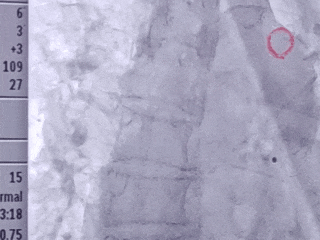

在超声下观察房缺封堵器形态

双孔房缺,术前彩超报两孔分别7.9mm和15.0mm,孔距6.3-8.4mm,选择MemoCarna氧化膜房缺封堵器DMFQFDQ-I 28,封堵后仍有2-3mm残余分流,对血液动力学没有影响,术者评估在允许范围

释放房缺封堵器

术后观察封堵器形态

左心耳封堵器稳定锚定在心耳内部

房缺封堵器稳定夹持房间隔